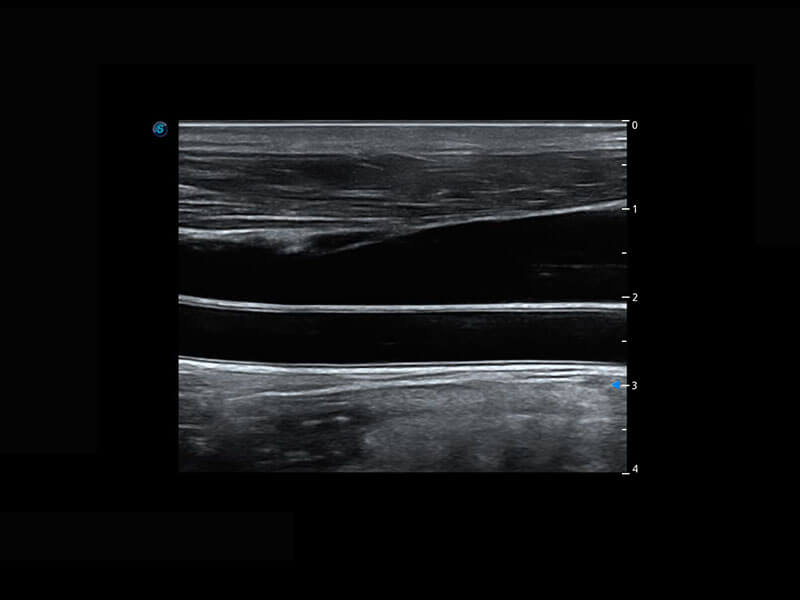

• 新生儿脊髓圆锥